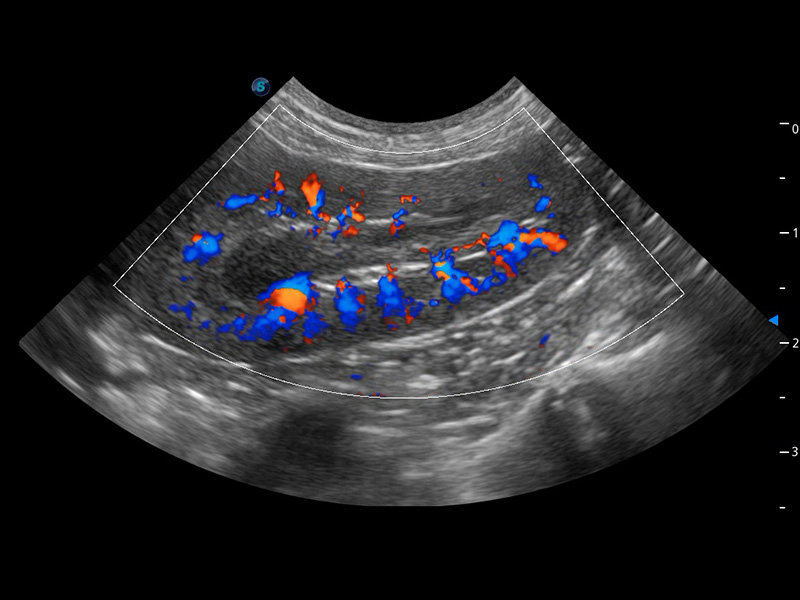

ProPet 60 作為一款高端臺(tái)式動(dòng)物超聲設(shè)備,為動(dòng)物醫(yī)生的日常診斷提供了一系列貼合動(dòng)物臨床需求、解決臨床實(shí)際問(wèn)題的高級(jí)成像功能。憑借全系列高清探頭,滿足醫(yī)生對(duì)腹部、心臟、生殖、淺表、肌骨等成像的所有需求,切實(shí)幫助您提升檢查效率,提高診斷信心。